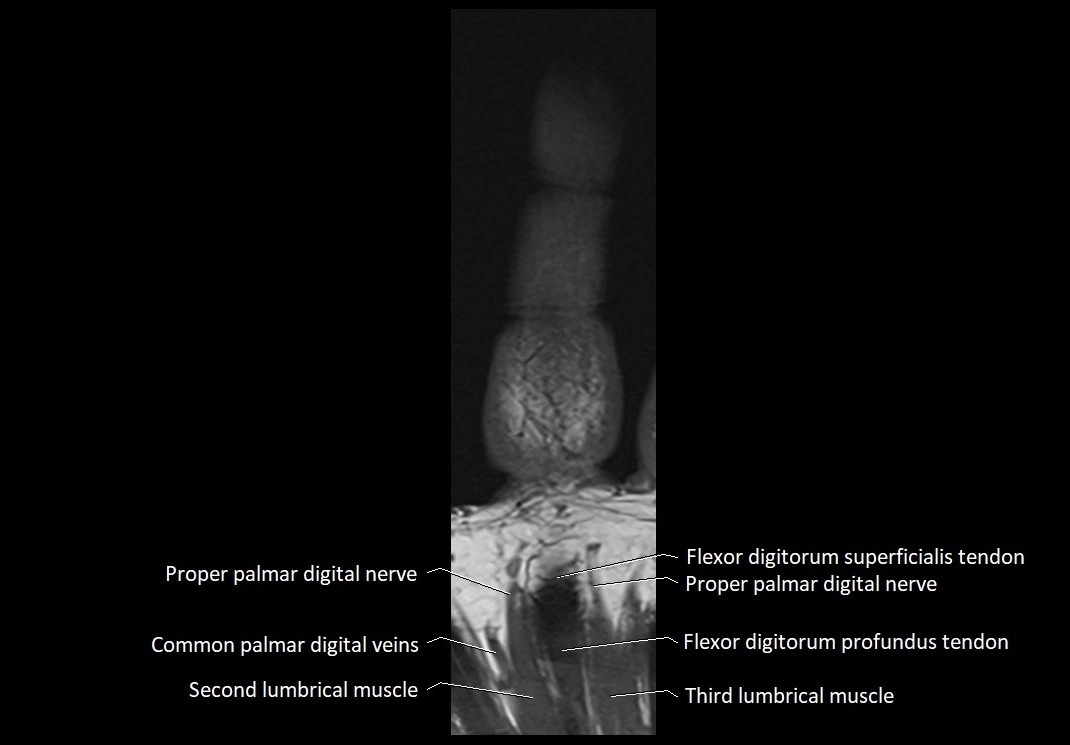

MRI images

image